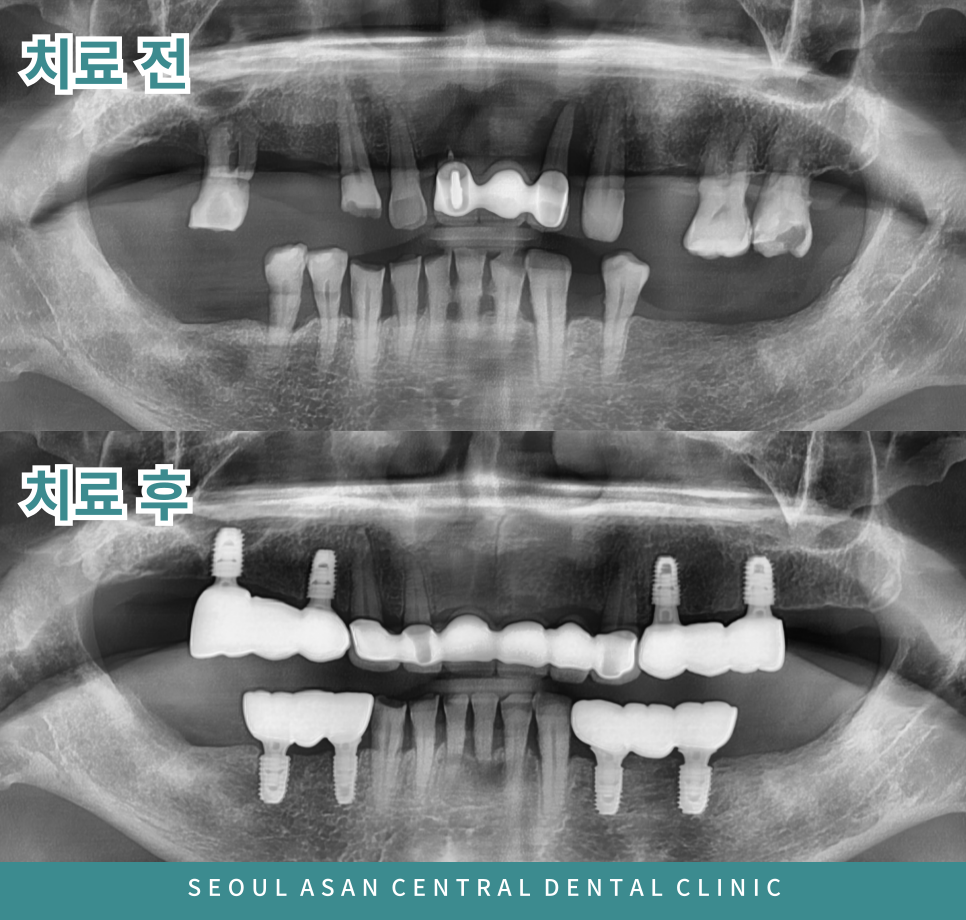

일부 치아는 이미 상실된 상태였으며,

남아 있는 잔존 치아들에서도 동요도가 관찰되었습니다.

이에 치료를 진행하기 전

파노라마 방사선 촬영을 통해

전반적인 구강 상태를 정밀히 파악한 후

치료 계획을 수립하는 것이 필요합니다.

특히 상악 전치부의 기존 보철물이 장착된 부위와

상·하악 양측 구치부의 잔존 치아들에서

동요도가 심한 경우,

해당 치아를 장기간 유지하기는 어렵다고 판단될 수 있습니다.

이러한 경우 예후가 불량한 치아들은 발치가 필요할 수 있습니다.

상실된 부위와 발치가 필요한 부위의 치아 수에 맞춰

임플란트를 식립하는 것이 이상적일 수 있으나,

환자분의 잇몸뼈 상태 등을 종합적으로 고려하여

치료 계획을 조정하게 됩니다.

이에 따라 상악 전치부는

기존 보철물이 씌워진 치아를 발치한 후,

인접 치아를 지대치로 활용한 브릿지 보철 치료를

진행하는 것이 보다 적절할 수 있습니다.